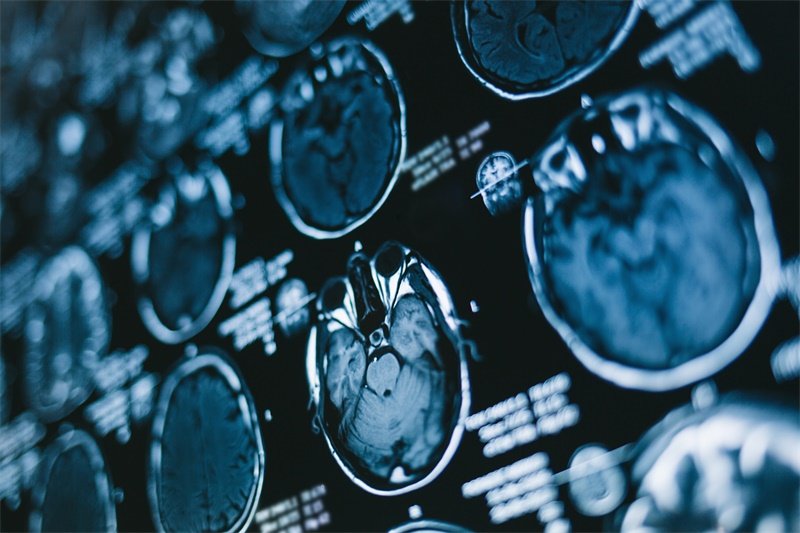

确诊垂体腺瘤一般采用影像学检查,常见的方式是核磁共振成像(MRI)。这种技术能够清晰地显示肿瘤的大小、位置及与周围神经和血管的关系。除了影像学评估,内分泌功能 tests(如血液化验激素水平)也至关重要,特别是在临床表现出内分泌症状的患者中。